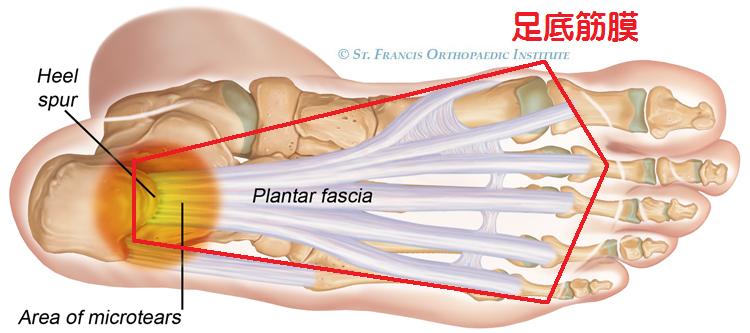

受動的支持組織とは、足底腱膜と底側踵舟靭帯で構成されていて、

- 足底腱膜=ウィンドラス機構と時に活躍します